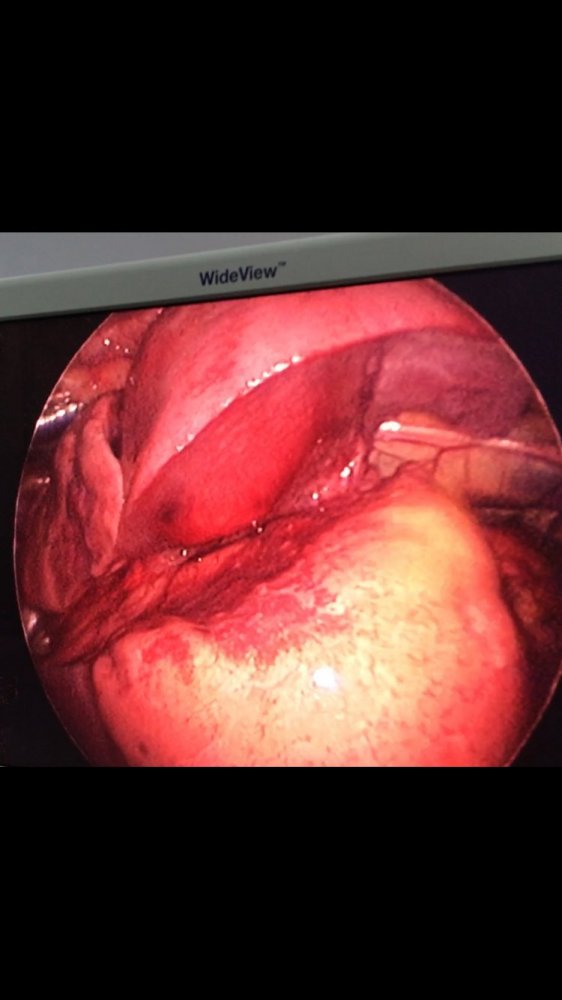

MediastinalTeratoma .Torokoskopik teratomanın eksiziyası

Daha bir çətin əməliyyat 8 yaşlı pasientdə döş boşluğunda törəmə- Ağciyərin orta payı üzərində böyük həcmli törəmə Teratoma. Torokoskopik törəmənin eksiziyası